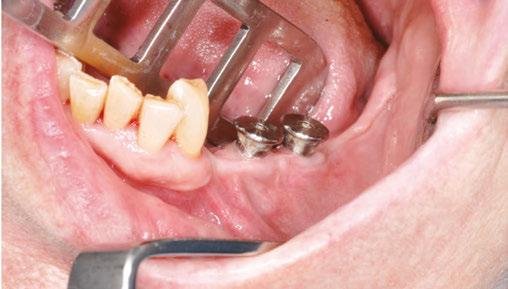

Our patient is consulting for pain in the right mandibular molar region and difficulty chewing (Figure 3).

Figures 2A and 2B: Panthera Dental platform interface; vestibular (2A) and lingual (2B) views of the subperiosteal implant Figure 3: Initial panoramic image Figures 4A-4C: Visualization of the subperiosteal implant in relation to the mock-up

not to undergo long and complex implant treatment. Her request is first and foremost functional. Esthetics and price are secondary concerns. We therefore offer the following treatment plan: keep the malpositioned anterior mandibular teeth with only mild gingivitis, rehabilitate the left posterior mandibular region with a subperiosteal implant, extract molars 47 and 48, and reassess the best implant solution for this region after healing.

Given the initial anatomical situation (strong resorption, significant mobile soft tissue, blockage by the tongue, V-shaped mandible), a conventional impression with a CIT and a physical mock-up with radiopaque markers are preferred.